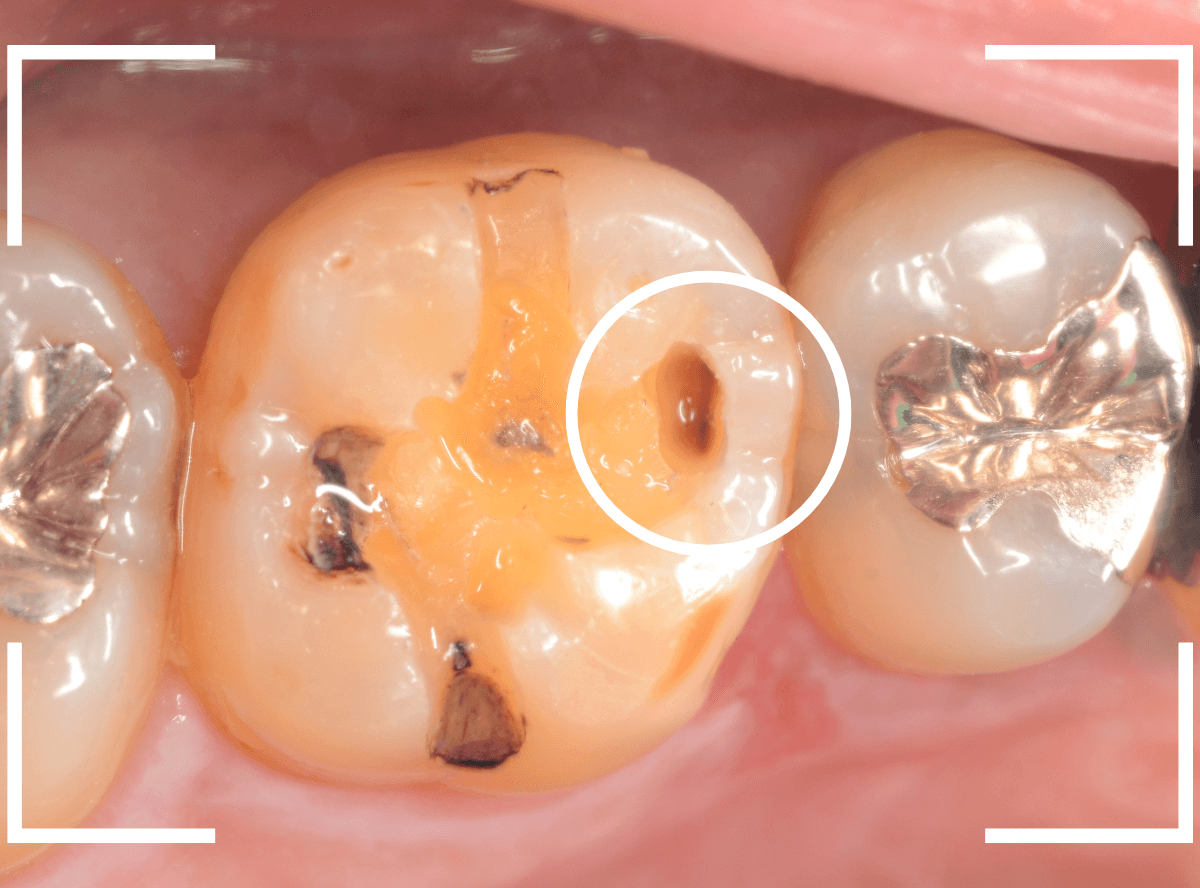

レントゲン写真では確認できませんでしたが、手前の小臼歯は深い虫歯でした。

このように、歯と歯の間の虫歯は、深い事が多いです。